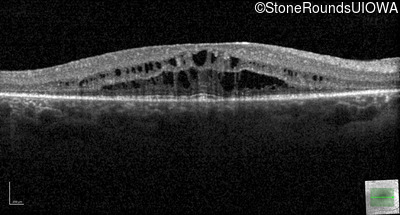

Optical Coherence Tomography - Left - 20/32

Exemplar / OCT Stack

OCT Stack